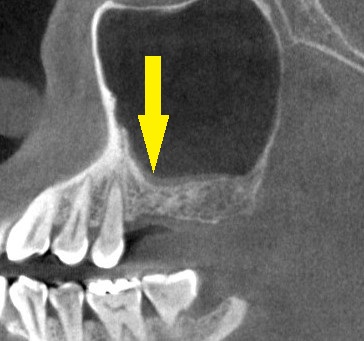

下段左の写真が手術前のCT、右が手術後のCTです。

インプラント周囲に白く写る人工骨が填入されいるのがお分かりいただけると思います。